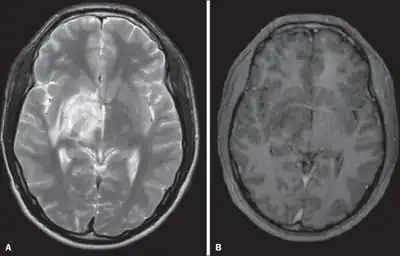

"...Despite its rarity, the patient's ethnic background and the typical radiographic findings should prompt the clinicians to include NBD in the differential diagnosis of optic neuritis and demyelinating disease in the young..."[5]. This quote indicates that even common symptoms such as headache should be recognized as the sign for possible NBD considering the patient's ethnic background.

- Koçer, N; Islak, C; Siva, A; Saip, S; Akman, C; Kantarci, O; Hamuryudan, V (Jun–Jul 1999). "CNS involvement in neuro-Behçet syndrome: an MR study". AJNR. American Journal of Neuroradiology. 20 (6): 1015–24. PMC 7056254. PMID 10445437. Archived from the original on 2023-09-30. Retrieved 2023-09-22.